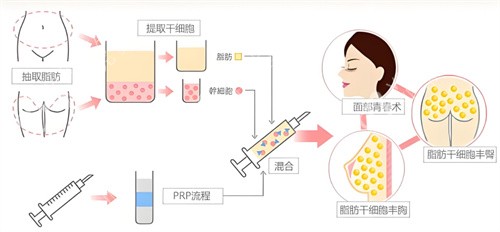

(一)“三维护活”技术,成活率超80%

他自创的“脂肪三维护活体系”,从提取、提纯到填充全程把控:取脂时用2.0mm超细钝针,配合“扇形低负压抽取”,减少脂肪细胞破损;提纯时采用“离心+过滤+静置”三重处理,去除油脂、血水等杂质,保留活性高的脂肪颗粒;

填充时用“多点、分层、微量”注射法,将脂肪均匀注入乳腺后间隙和皮下层,避免堆积形成结节,不少求美者反馈术后3个月成活率高,基本一次就能达到理想罩杯。